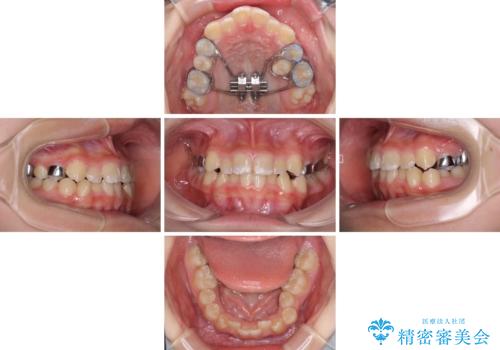

- 急速拡大装置・インビザライン

- 小児矯正の頃から診察を行っている患者様です。

上顎骨の幅が下顎骨よりも小さいので、拡大装置により骨幅を広げて上下関係を改善し、その後インビザラインにて歯並びを整えることとしました。